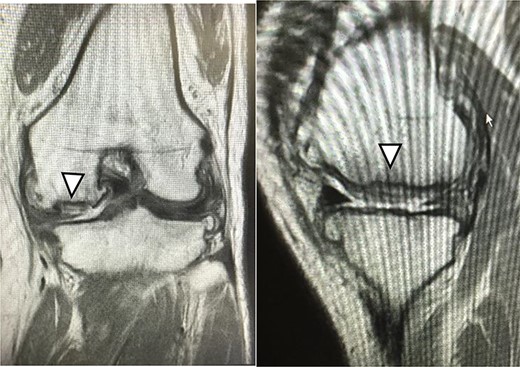

MRI findings at 1 year after the surgery indicated signal intensity area in the grafted area for the patient with JACC (Fig. 8), whereas the patient who underwent Reveille CP exhibited greater thickness at the grafted area as compared to the surrounding healthy cartilage (Fig. 9). The MOCART score at 1 year after the Reveille CP surgery (60 points) was higher than that of JACC (50 points).

One year after JACC, MRI showed T2 high intensity area in the graft area (arrowhead).

One year after Reveille CP. The graft area was thicker than surrounding healthy cartilage (arrowhead).

Five years after JACC. MRI showed the graft area was thicker than the surrounding healthy cartilage (arrowhead).